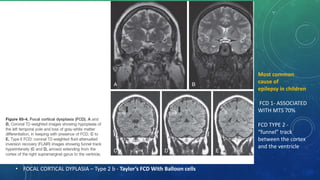

• FOCAL CORTICAL DYPLASIA – Type 2 b - Taylor’s FCD With Balloon cells

Most common

cause of

epilepsy in children

FCD 1- ASSOCIATED

WITH MTS 70%

FCD TYPE 2 -

“funnel” track

between the cortex

and the ventricle